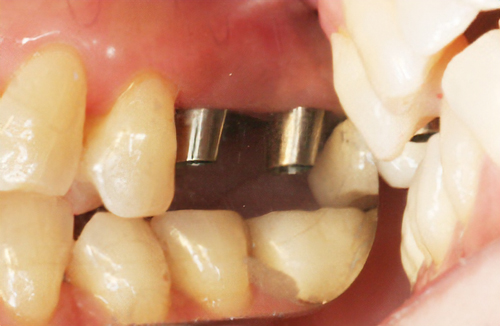

• 審美面も機能面でも回復

インプラントとは、失ってしまった歯の代用として、人工歯根=インプラントを埋め込む方法です。この人工歯根の上に、セラミックなどの被せ物を装着することで、審美面も機能面でも回復する方法です。

土台